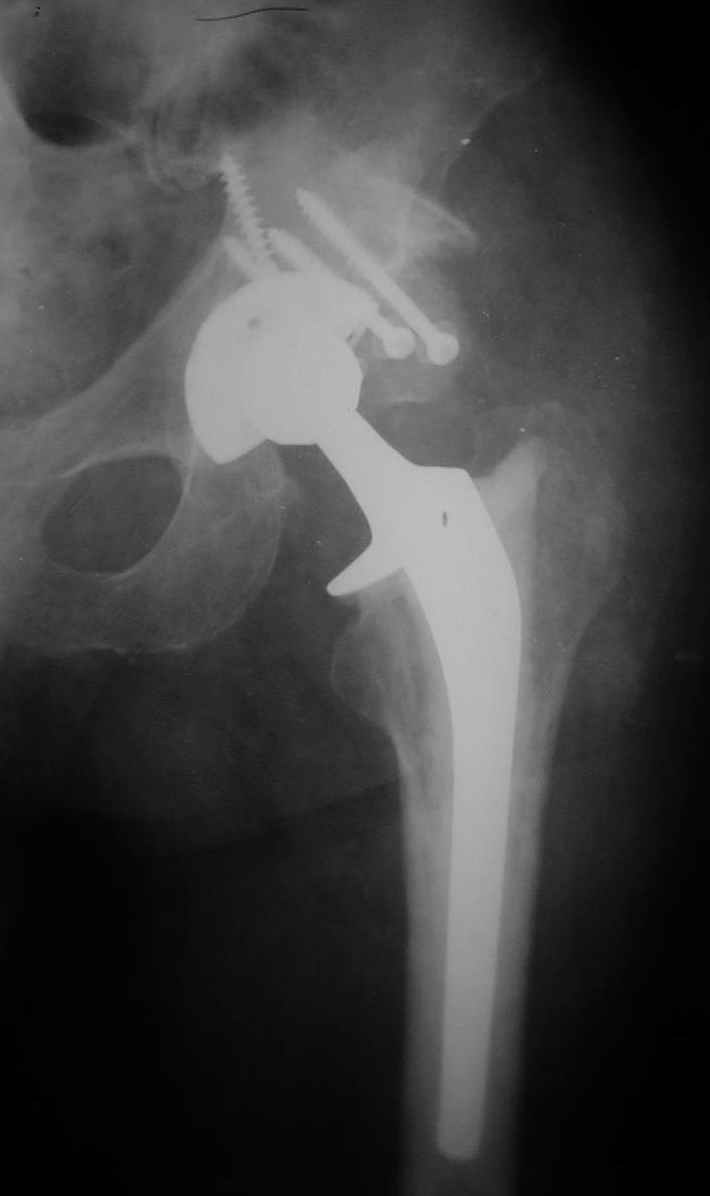

В институте совместно с фирмой Зиммер достаточно регулярно (практически ежемесячно) проводятся 2-х недельные циклы по различным вопросам эндопротезирования. Если есть возможность и желание, мы готовы поделиться с Вами нашим опытом, тем более есть что показать и что обсудить - в настоящее время ежедневно выполняется от 6 до 10 эндопротезирований коленного и тазобедренного сустава. В качестве примеров хочу показать 2 наблюдения, через 1 год и 5 лет после операции

1 год

5 лет